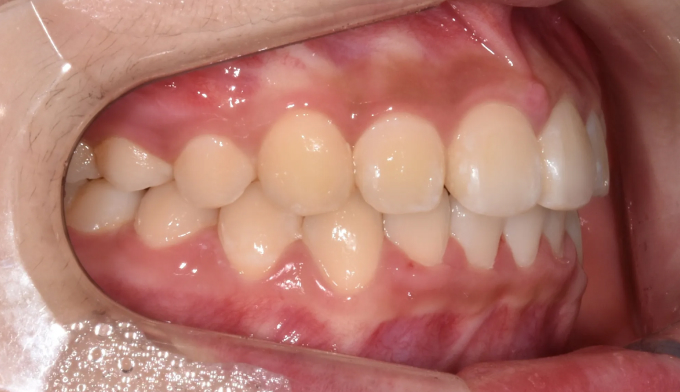

위턱, 아래턱 모두 치아 배열 공간이 부족한 경우 입니다.

확장장치를 이용해 공간 부족을 해결하고 치열을 배열하면 간단히 끝낼 수 있습니다.

이때 입술의 두께나 위치, 위아래 앞니의 각도를 종합적으로 고려하여야 합니다.

치아를 배열한다고 앞니가 뻐드러지면 잘못된 교정치료입니다.

총 치료기간은 20개월 소요되었습니다.